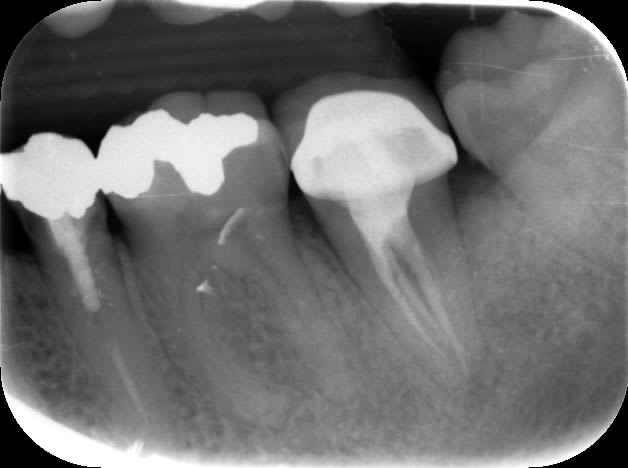

Endo 37 canal secondaire vers espace interradiculaire?

exemple bis